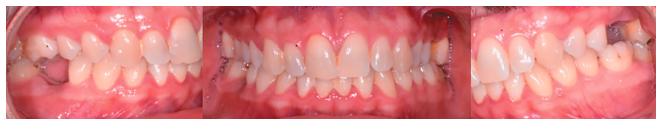

En la Historia Clínica no se evidenciaron antecedentes médico-quirúrgicos de interés, alergias medicamentosas conocidas ni hábitos nocivos. En la exploración extraoral no se apreciaron datos relevantes. En la exploración intraoral se apreciaron dientes no restaurables en posición de 2.6 y 4.6 y la presencia de los terceros molares inferiores retenidos. (Figuras 1 y 2).

En la exploración radiográfica, mediante radiografía panorámica, se apreciaron ambos terceros molares inferiores retenidos, en posición horizontal (Figura 3), e imágenes radiolúcidas apicales en posición de 2.6 y 4.6. En el escáner de haz cónico se evaluó la morfología radicular del tercer molar superior izquierdo, y la dimensión de la lesión radiolúcida apical del primer molar superior izquierdo (Figura 4), datos necesarios para valorar el grado de adaptación del diente donante en el lecho receptor.